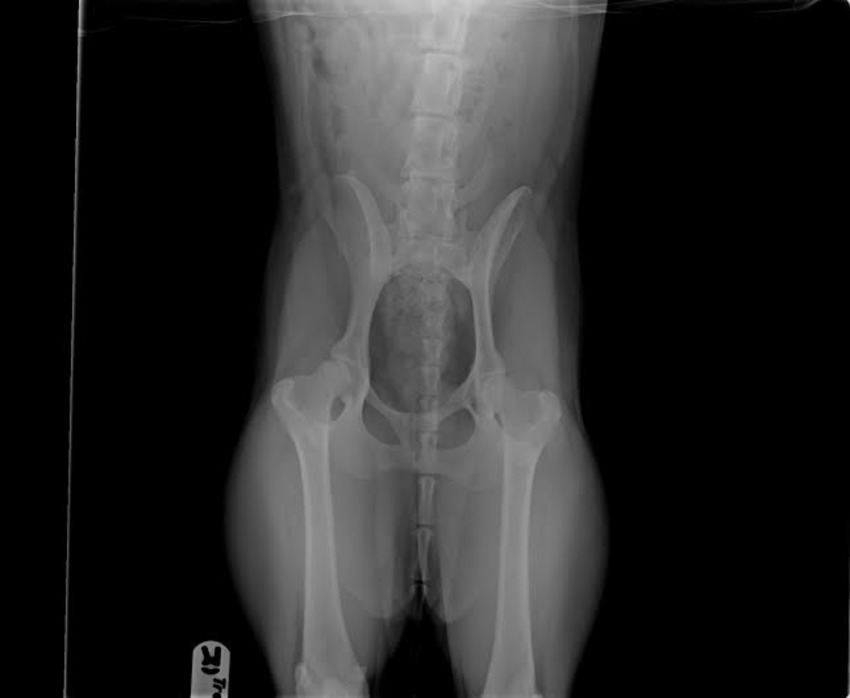

Oh! En bijna vergeten te melden; Charlie is helemaal HD vrij! We moesten het voor de behendigheid laten testen en ben daar toch wel super blij mee natuurlijk

(de foto is niet helemaal recht genomen, omdat ik haar geen roesje wou geven

)